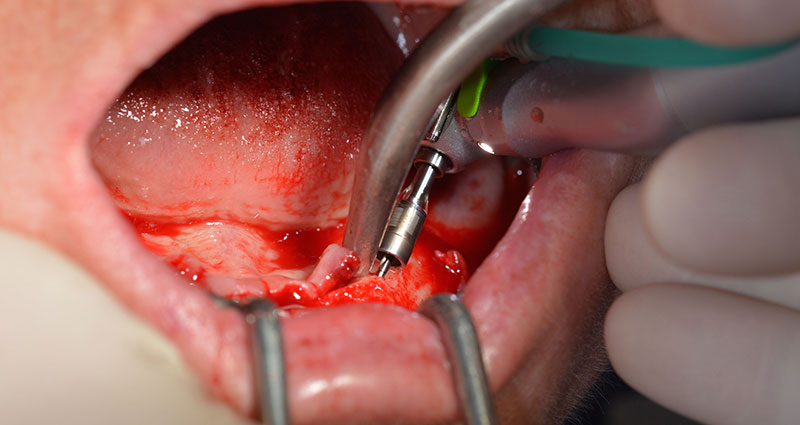

Das chirurgische Protokoll der verwendeten Implantate (SKY, bredent medical) schreibt eine Umdrehungszahl von 1.200/min für die Pilotbohrungen vor (Abb. 7–9).

Dies entspricht der nächsten Position der Voreinstellung am Implantmed. Zu erkennen ist die etwa 45-Grad-Schräghaltung des W&H Winkelstückes nach mesiokaudal in Regio 45, um den Nervus mentalis zu schonen. Das Foramen mentale gilt als anatomische Orientierung für alle Bohrungen in diesem Bereich. Die anschließenden Bohrungen werden mit einer reduzierten Umdrehungszahl von 300/min durchgeführt (Abb. 10 und 11).